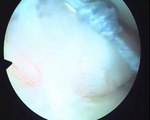

Arthroscopic shoulder surgery for shoulder dislocation. 8